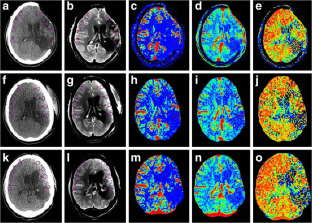

We prospectively investigated six stable TBI patients who underwent cranioplasty more than 90 days after effective decompressive craniectomy. Computerized tomography perfusion (CTP) studies and evaluation of clinical outcome were performed for each patient before cranioplasty and at 7 days and 3 months after surgery. Cerebral blood flow (CBF), cerebral blood volume (CBV) and mean transit time (MTT) were measured in multiple cortical circular regions positioned in cranioplasty-treated and contralateral hemispheres.

Neither complications associated with cranioplasty nor changes in outcome were observed. On the treated side, CBF and CBV values were higher before and 7 days after cranioplasty than at 3 months after surgery, whereas MTT values were lower at 7 days than at 3 months after surgical treatment.

Our results indicate that cortical perfusion progressively declines in the cranioplasty treated hemisphere but remains stable in the contralateral hemisphere after surgery and suggest that CTP can represent a promising tool for a longitudinal analysis of hemodynamic abnormalities occurring in TBI patients after cranioplasty. In addition, these data imply a possible role of cranioplasty in restoring flow to meet the prevailing metabolic demand.